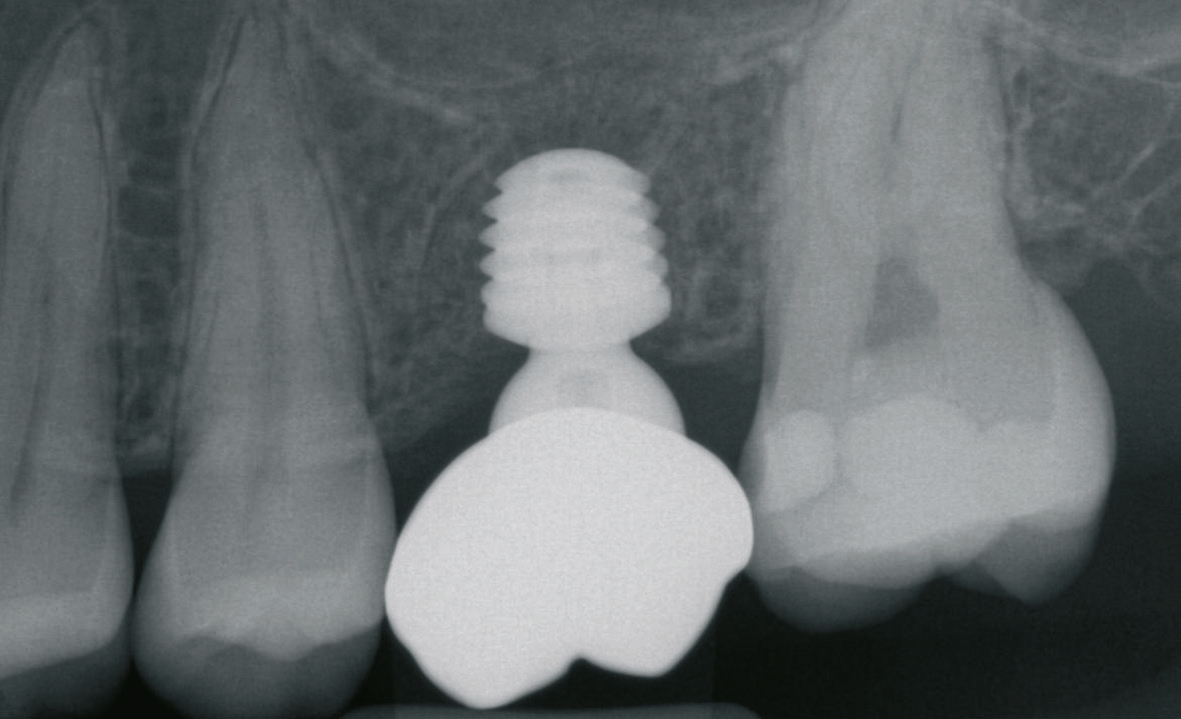

Eine der häufigsten Indikationen für Implantate überhaupt stellt die Einzelzahnlücke nach Verlust eines ersten Molaren dar. Bei den meisten Fällen liegt ein stabiles vertikales Knochenangebot an den Nachbarzähne vor, sodass in der Regel nach Ausheilung des apikalen Granulationsgewebes von einer guten Knochenregeneration auszugehen ist, so dass keine Notwendigkeit der Insertion von kurzen oder ultrakurzen Implantaten gegeben ist. Im Oberkiefer kann bei einer weiten Divergenz der Wurzeln des extrahierten Zahnes es zu einer ausgeprägten Pneumatisation der Kieferhöhle kommen. Daher werden gerade beim jugendlichen Patienten dort dann kurze Implantate eingesetzt, um auf eine Sinusbodenelevation mit einem lateralen Zugang verzichten zu können [3]. Die Implantate können mit oder ohne eine Navigationsschablone gesetzt werden [4]. Da die Lücke begrenzende Nachbarzähne eine gute Orientierung in der mesio-distalen Dimension ermöglichen, kann oftmals auch auf eine Orientierungsschablone verzichtet werden. In der oro-vestibulären Richtung muss der Anwendung des größeren Durchmessers Rechnung getragen werden. Dies kann mit einfachen Positionierungshilfen erfolgen, damit die Implantatachse möglichst zentral in der Kaufläche zu liegen kommt (Abb. 1-8). Die Einzelzahnlücke kann mit einer integrierten verschraubbaren Abutment-Hybrid-Krone oder mit einem Abutment und einer zementierten Krone versorgt werden [5].